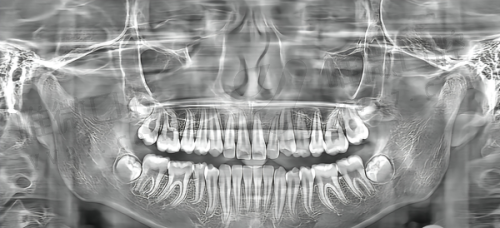

特别多人以为“种植牙=一颗牙”,其实它是个「三位一体」的组合:种植体(埋在骨头里的“牙根”)+ 基台(连接种植体和牙冠的“中间件”)+ 牙冠(露在外面的“牙齿”)。每一部分的材料、工艺、品牌不同,价格都会“跳级”——

比如种植体是核心中的核心:进口一线品牌(如瑞士ITI、瑞典诺贝尔)采用四级纯钛+亲水涂层,能快速和骨头“长在一起”(骨结合率>98%);而小品牌种植体可能用二级纯钛,表面处理粗糙,不仅修复慢,还可能出现松动。再比如牙冠:全瓷冠(二氧化锆材质)比烤瓷冠(含金属)贵一倍,但生物相容性更好、更美观,还不影响核磁共振。

3. 术前检查:300-500元——包括口腔CT(看骨量)、验血(查凝血功能)、口内扫描(设计方案),是“必须项”,能避免手术风险。